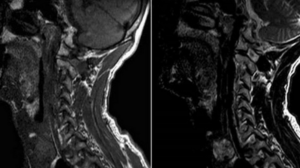

Диагностика щитовидной железы при помощи МРТ

Магнитно-резонансная томография (МРТ) щитовидной железы — метод диагностики, позволяющий получить точную информацию о развитии и строении органа, форме, размерах, патологических изменениях тканей, а также выявить новообразования. Никакого вреда организму такое исследование не наносит. Ценность метода МРТ при исследовании щитовидной железы имеет следующие преимущества: Достоверность результатов, благодаря которым врач делает выводы о состоянии органа. Без радиации. …